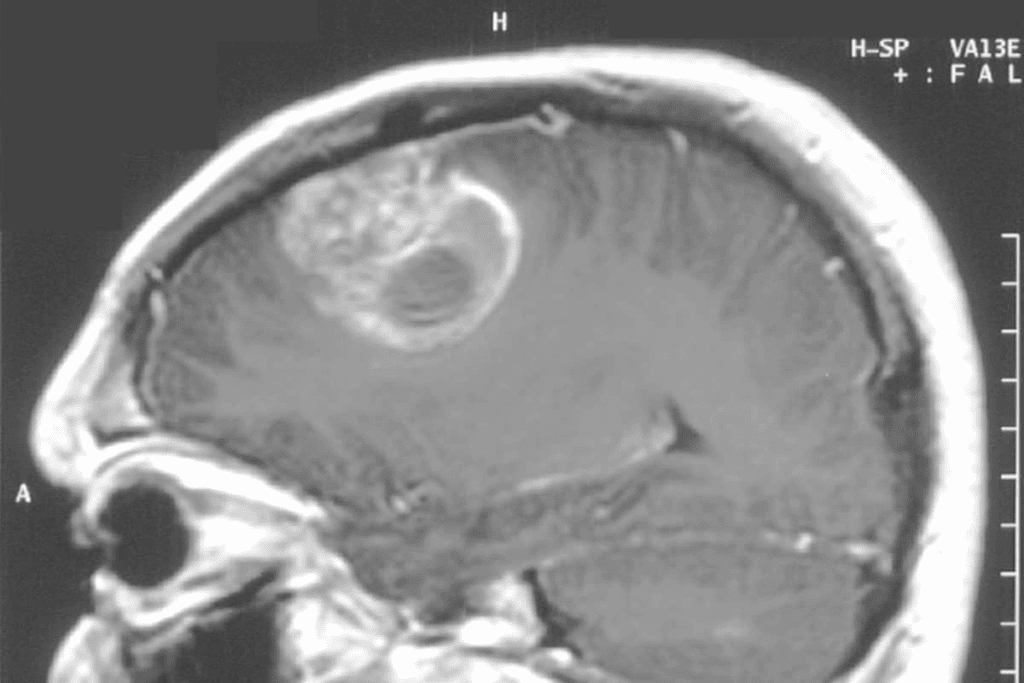

Types of MRI Scans Used for Brain Tumor Diagnosis

Diagnosing brain tumors needs different MRI scans. Each scan gives unique insights into the tumor. The choice depends on the tumor type, location, and the patient’s health.

Standard MRI vs. Functional MRI

Standard MRI shows the brain’s structure. It helps doctors spot abnormalities. Functional MRI (fMRI) looks at brain activity by tracking blood flow changes.

fMRI is key for planning surgery. It shows how tumors affect brain function. This info is vital for treatment planning.

Contrast-Enhanced MRI Techniques

Contrast-enhanced MRI uses a contrast agent to highlight brain areas. It’s great for spotting different tumors and their boundaries.

The contrast agent shows up in areas with blood-brain barrier issues. This makes tumors stand out on MRI images. It boosts diagnostic accuracy and helps plan treatment.

Brain Tumor Staging Using MRI Technology

MRI has changed how we stage brain tumors, giving us detailed views of tumors. It’s key in diagnosing and staging brain tumors. This helps doctors decide the best treatment.

How MRI Helps Determine Tumor Grade

MRI is key in finding out how aggressive brain tumors are. It helps doctors see important details like:

- Tumor size and location

- How the tumor reacts to contrast agents

- Presence of dead tissue or cysts

- How much the tumor affects the brain

These details help doctors figure out the tumor’s grade. High-grade tumors need stronger treatments. Low-grade ones might get milder care.